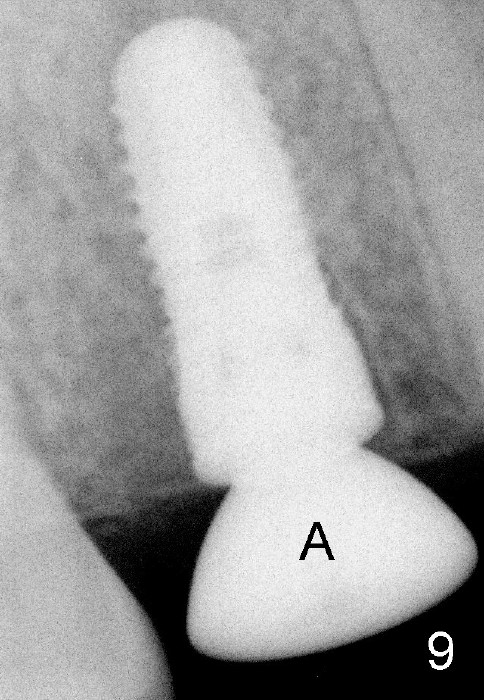

Fig.9: The density of the distal socket increases 2.5 months postop. A: healing abutment.